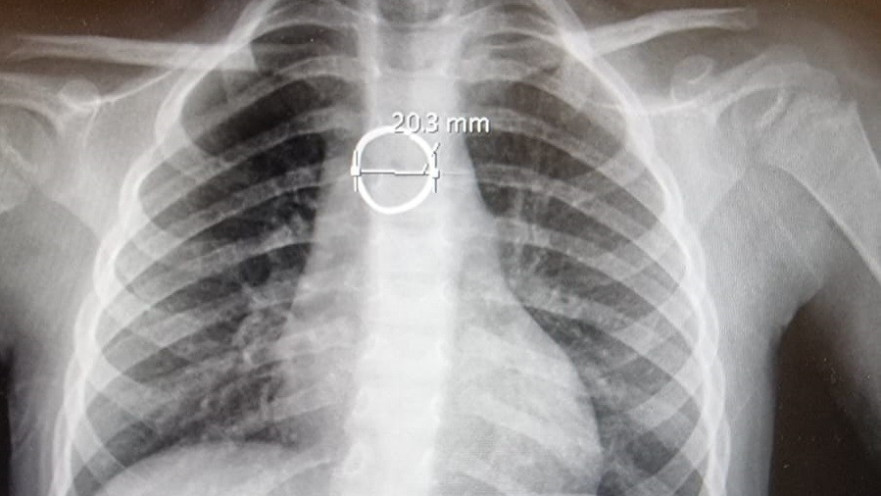

צילום הרנטגן בו נצפתה הטבעת | צילום: באדיבות בית החולים הלל יפה

הקטינה הוכנסה לניתוח חירום תחת הרדמה מלאה, ובאמצעות אנדוסקופ (צינור צר וגמיש) שהוכנס דרך חלל הפה לוושט, הצליח ד"ר סוהיל גרה, רופא במחלקת אף אוזן גרון, לשלוף את הטבעת בשלמותה. דימה אושפזה להשגחה במחלקת ילדים כשהיא מרגישה טוב. לגבי הטבעת - הבת תשמור אותה למזכרת בתוך קופסה קטנה.